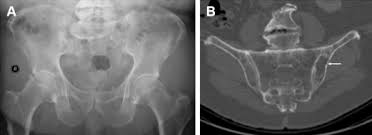

} myeloma cells produce paraproteins which are found in blood and urine (protein bence jones). The pelvis contains numerous lytic lesions without reactive sclerosis which have multiple myeloma. Healthy plasma cells help you fight infections by making antibodies that recognize and attack germs. Spotlight revised international staging system for multiple myeloma: Multiple myeloma is a cancer of plasma cells, which are white blood cells found mainly in the bone marrow. If you still can't find it, please let us know so we can add it!. Other tests include blood monoclonal immunoglobulin and radiology tests to determine the extent of bone lesions. Multiple myeloma is the second most common type of blood cancer after leukemia. 1,2,3 it accounts for approximately 1% of all malignant. Treatment response, detection of relapse. International myeloma working group molecular classification of multiple myeloma: It accounts for approximately 10% of all. Extraosseous myeloma refers to any manifestation of multiple myeloma where there is plasma cell proliferation outside the atypical manifestations of multiple myeloma:

Multiple myeloma is a cancer of plasma cells, which are white blood cells found mainly in the bone marrow. Find more information on clinical trials that are open for enrollment at mount sinai's center for excellence for multiple myeloma. Multiple myeloma (mm), also known as plasma cell myeloma and simply myeloma, is a cancer of plasma cells, a type of white blood cell that normally produces antibodies. Treatment response, detection of relapse. Related online courses on physioplus. 16,000 new cases and 11,000 deaths. Changing the treatment landscape for hematologic malignancies learn more. In multiple myeloma, when the cancer protein level is up, the normal antibody levels are down. If you still can't find it, please let us know so we can add it!. Tell the radiologist or the radiology technician about your diagnosis before receiving dye injection into. It accounts for approximately 10% of all. Other tests include blood monoclonal immunoglobulin and radiology tests to determine the extent of bone lesions. Spotlight revised international staging system for multiple myeloma: